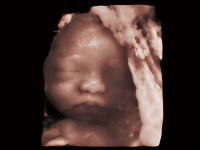

作为开立医疗全新打造的超高端旗舰超声产品,从探头抬起唤醒开启扫查到多维探头发射接收,通过先进的场成像发射、自适应聚合重建等技术,基于RF Data原始射频数据在图像生成、高端功能等方面实现突破,为妇产科、儿科提供全方位临床解决方案。

梦溪®P80以“关爱女性”为基石,提供全方位的解决方案,量身定制以满足女性的健康需求,涵盖妇科、生殖健康检查、产前筛查及产后康复等领域。